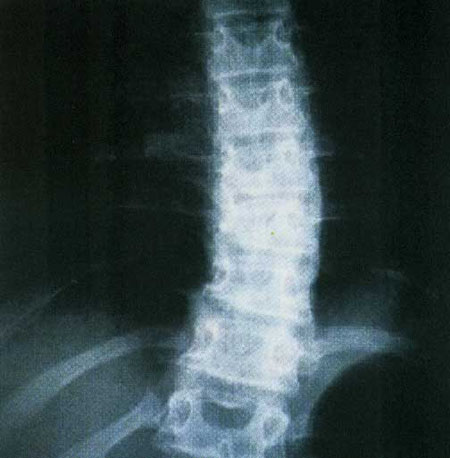

سر انسان بالغ بين 10 تا 14 پوند(برابر با 4/5 تا 6/3 کيلوگرم) وزن دارد؛ تقريبا به اندازه يک توپ بولينگ متوسط. هنگامي که سر درست بالاي گردن و شانه ها قرار مي گيرد، اين وزن بين تمام ماهيچه هاي آن قسمت به طور متوازن پخش مي شود و به هيچ ماهيچه اي فشار بيش از حد وارد نمي شود. اما وقتي توي مترو نشسته ايد و روي گوشي موبايلتان قوز کرده ايد، اوضاع کمي فرق مي کند.

تيم هاچفول، متخصص فيزيوتراپي، در اين مورد مي گويد:«در اين حالت ماهيچه هاي پشت گردن براي تحمل کردنِ وزن اين توپ سنگين بايد فشار بسيار زيادي را متحمل شوند. اگر به طور مداوم در اين حالت قرار نگيريد، مشکلي پيش نمي آيد. مشکل زماني بروز مي کند که مدت زمان زيادي دراين حالت قرار بگيريد. اگر هر روز به مدت طولاني در اين حالت قرار بگيريد. ماهيچه هاي شما به اين حالت عادت مني کنند و انعطاف پذيرشان کم مي شود.» هاچفول براي غلبه بر اين مشکل حرکت کششي معکوس را پيشنهاد مي کند:«بايد سعي کنيد شانه هايتان را به عقب خم کنيد و سرتان را بالا ببريد، مانند زماني که به چيزي در بالاي سرتان نگاه مي کنيد بايد براي 10 تا 20 ثانيه در اين حالت بماند. اين درست برعکس حالت قوز کردن است. حالا وقتي دوباره مشغول بازي مي شويد، طوري بنشينيد که پشت تان به پشتي صندلي بچسبد. موبايل را هم درست روبه روي خودتان بگيريد، به طوري که مجبور نباشيد، سرتان را خم کنيد.» در سايت زير مي توانيد تمرين هاي بيشتري براي جلوگيري از قوز کردن را پيدا کنيد: